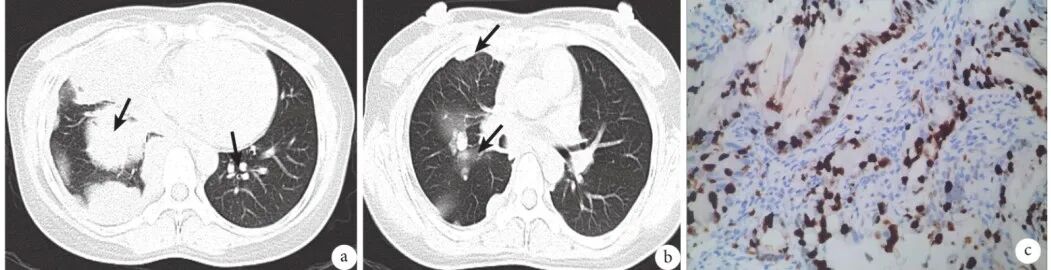

图3 晚期多发转移肺癌患者影像学表现及病理

a:该结节(箭头)长4.61 cm×4.81 cm,有明显的分叶、毛刺和血管集束征,CTR>50%,伴有多发胸膜转移,组织病理学证实为IAC,Ⅳ期;b:Ki-67表达50%(×200);CTR:实性成分比例;IAC:浸润性腺癌